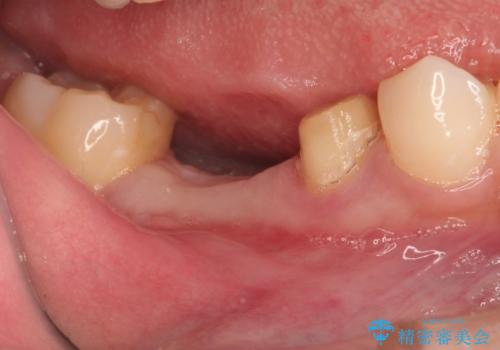

- 右下の奥歯の調子がよくないとのことで来院されました。

レントゲン・口腔内診査をお行い、保存が難しいことがわかりました。

抜歯後インプラントをする計画としました。